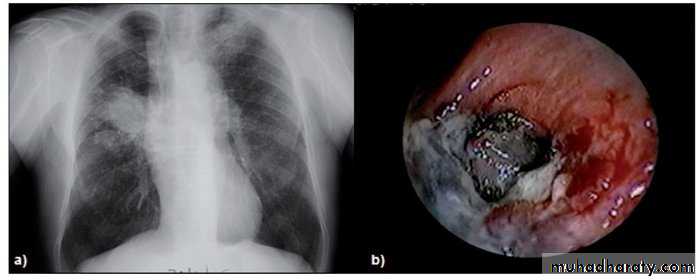

Abnormal chest X-ray at presentation with lower zone bi-basal reticular and reticulonodular opacities. 'honeycomb' appearance in advanced disease.

HRCT may be diagnostic, demonstrating a patchy, predominantly peripheral, subpleural and basal reticular pattern with subpleural cysts (honeycombing).

BAL (bronchoalveolar lavage) and transbronchial biopsy may be used to exclude alternative diagnoses. Not require in typical clinical features and HRCT.